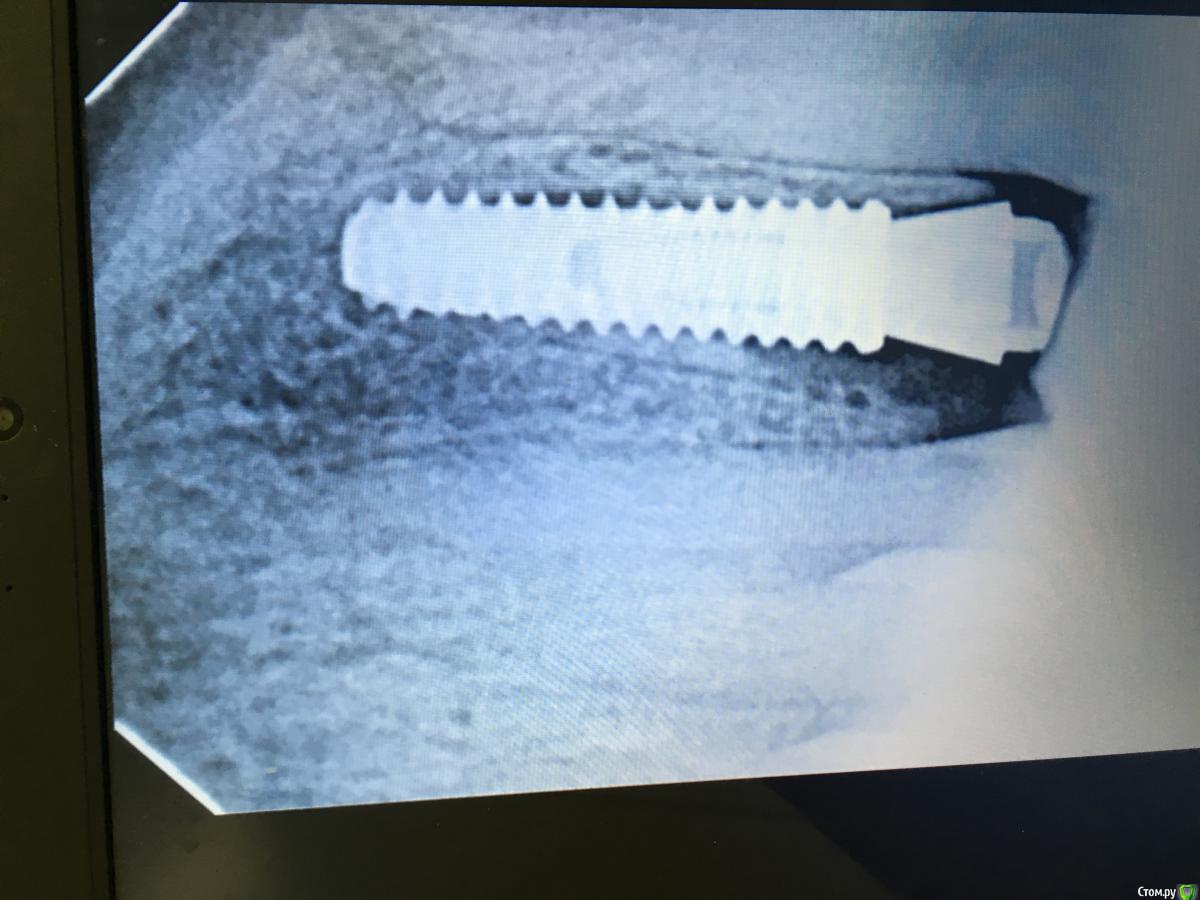

Evikrol Опубликовано 27 августа, 2018 Поделиться Опубликовано 27 августа, 2018 (изменено) Мой имплант на месте. Вот уже оттиск снял. Ждал 5 месяцев Изменено 27 августа, 2018 пользователем Evikrol Ссылка на комментарий

Evikrol Опубликовано 27 августа, 2018 Поделиться Опубликовано 27 августа, 2018 Даже не спрашивайте как я его не заметил. Вообще не самая удачная работа. 12 неподвижен. 1 Ссылка на комментарий

Evikrol Опубликовано 1 сентября, 2018 Поделиться Опубликовано 1 сентября, 2018 13 сентября будем нагружать. Ссылка на комментарий